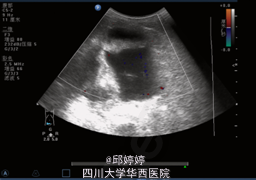

腹部膨隆,下腹部压痛,无肌紧张及反跳痛,余无特殊。超声检查:腹内查见巨大囊性团块,上至剑突下至盆腔,大小约11.5x12.5x9.2cm,边界清楚,形态较规则,内可见粗大条状分隔,内未见明显血流信号:腹腔内分隔囊性占位,性质?(图1,2)